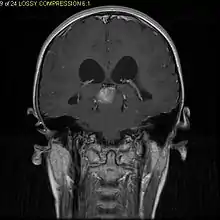

Pilocytic astrocytomas are often cystic, and, if solid, tend to be well-circumscribed. They are characteristically easily seen on computed tomography (CT scans) and magnetic resonance imaging (MRI).

Usually – depending on the interview of the patient and after a clinical exam which includes a neurological exam and an ophthalmological exam – a CT scan and/or an MRI scan will be performed. A special dye may be injected into a vein before these scans to provide contrast and make tumors easier to identify. The neoplasm will be clearly visible.